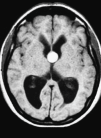

Quiste coloide del III ventrículo e hidrocefalia.

Fig. 1.